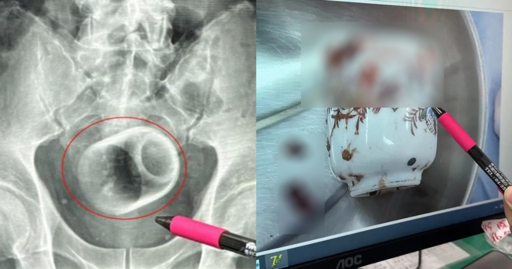

Man in Taiwan somehow gets 8cm by 6cm ceramic cup in bottom, claims it got there 'by accident'